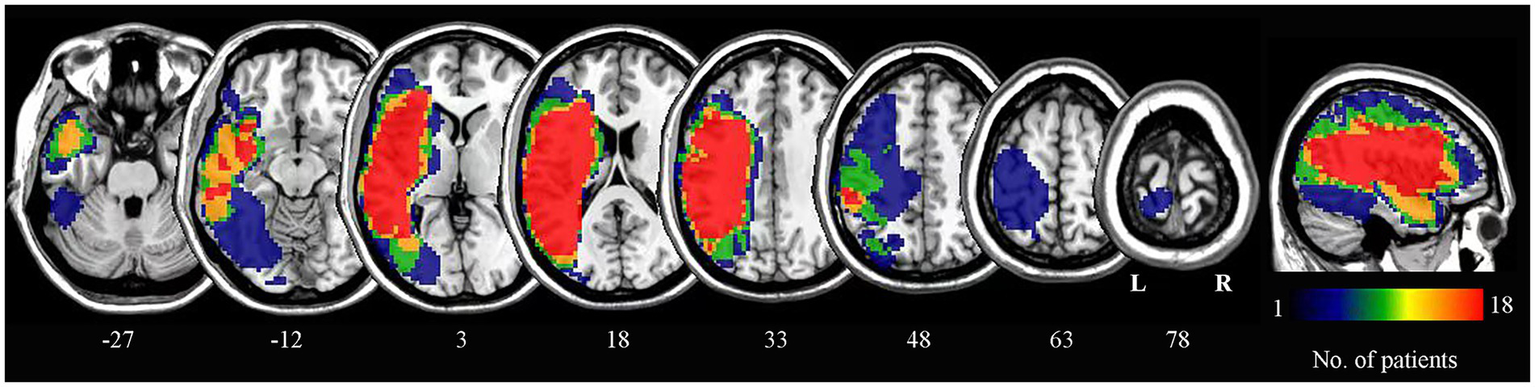

2.5 Lesion overlap map

Lesion outlines were manually traced by a trained researcher on individual 3D T1-weighted structural images using the pen tool in MRIcron software to create a lesion mask for each patient. The transformation matrix derived from normalizing the individual 3D anatomical images to standard space was then applied to normalize each lesion mask to the same standard space. The normalized lesion masks from all patients were overlaid to construct the lesion overlap map (Figure 1).

Figure 1

Lesion overlap map for all patients. The numbers below each axial slice correspond to z-plane coordinates in MNI space. The color scale indicates the number of patients with lesions in each voxel. L, left; R, right.